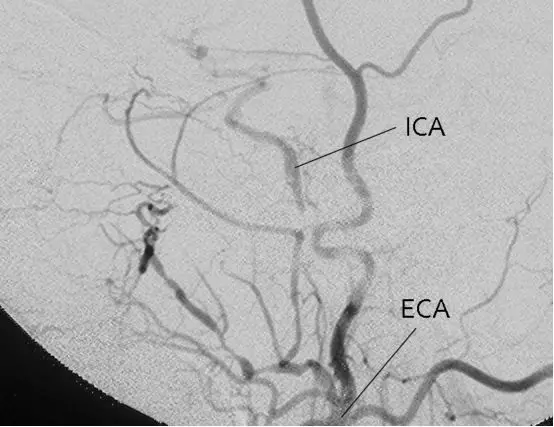

颈内动脉闭塞,来自上颌内动脉分支的代偿。a,颈总动脉造影侧位,眼动脉由脑膜泪腺动脉(单箭)和脑膜回返动脉(双箭)代偿。通过圆孔动脉(箭头)代偿血流至下外侧干(Tanoue 2013)。

b,颈总动脉造影,动脉早期,侧位,颈内动脉发自翼管动脉(箭头)(Tanoue 2013)。

c,颈总动脉造影,动脉晚期,侧位,显示远端颈内动脉(Tanoue 2013)。